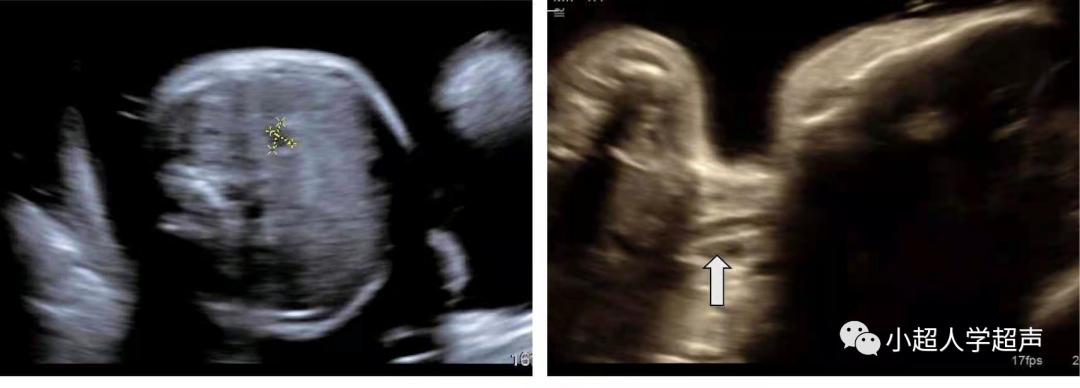

直接征象 :食道盲端的囊袋征,胎儿颈部的囊性结构

产前超声很难显示食管闭锁部位,所以很难进行准确的分型,常常通过羊水过多、胃泡不显示、腹围小等一些间接征象并动态观察胎儿吞咽羊水时是否出现颈部的“囊袋样”无回声来提示食管闭锁,因此产前超声对食管闭锁的检出率各家报道不一,大多不超过50%。

- 在早孕期(12--16周)采用经阴道探头观察食道比晚孕期容易

- 晚孕期则可用高分辨线性探头观察

食管闭锁的“囊袋样”无回声在检查过程中会观察到无回声结构 随胎儿吞咽动作大小有所改变 。